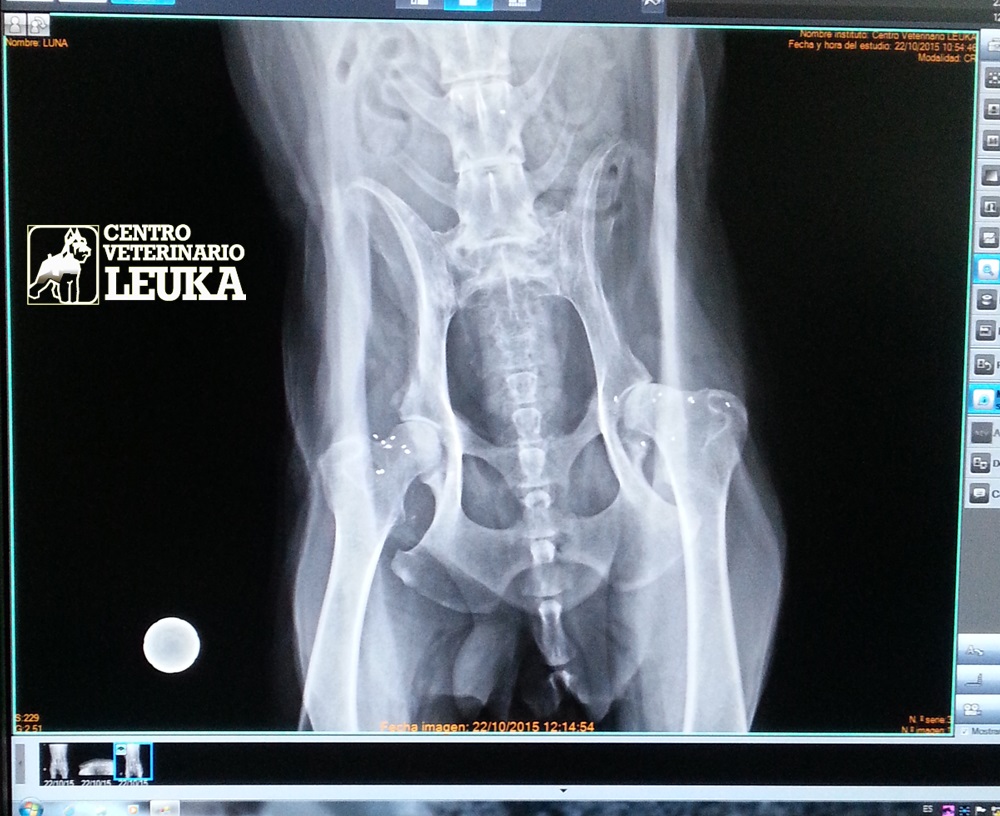

Son

pequeños fragmentos de hilo de oro de 24 quilates, que se implantan

en las zonas cercanas a las articulaciones dolorosas.

- Para

tratar el dolor articular en perros y gatos que sufren artrosis:

caderas, rodillas, codos, hombros, columna.

prevenir la artrosis en las articulaciones que sufren Displasia

(cadera, codo,...).